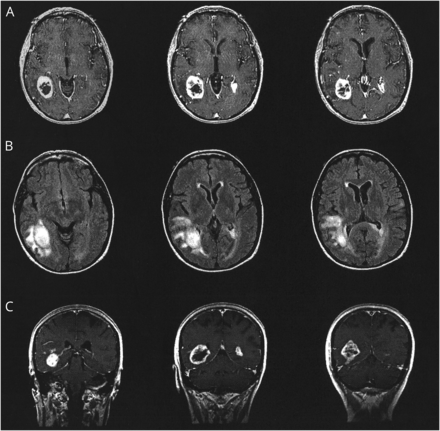

病人被称为大脑的核磁共振扫描来评估颅内异常。MRI显示变化符合多焦bihemispheric高档神经胶质瘤(图)。有一个大的提高区域周围水肿的temporo-occipital叶。这是最著名的网站。第二个增强病灶位于左顶叶白质与扩展在胼胝体压部。也有不正常的信号出现在T2 fluid-attenuated反转恢复图像涉及左额叶脑回。基于这些发现,病人被称为活组织检查。在高等院校,她提到了活组织检查,她的神经系统检查是重要的只剩下了视觉注意力不集中,同时两国刺激,建议左hemispatial忽视,除了面容失认症。活组织检查的权利temporo-occipital肿瘤显示多形性成胶质细胞瘤。放疗和化疗的病人被称为。

轴向超声造影被宠坏的梯度回忆图片(A),轴向fluid-attenuated恢复图像(B)和日冕对比度增强t1加权自旋回波图像(C)展示多个充当群众涉及右temporo-occipital叶和左顶叶心房区域。占主导地位的大众正确的temporo-occipital叶与温和的周围的水肿和质量效应。这种病变活检和显示多形性成胶质细胞瘤。

类固醇治疗后后续的化疗病人的面孔识别能力回来了。减少后续大脑成像显示周围的水肿和右侧病变的肿瘤大小。